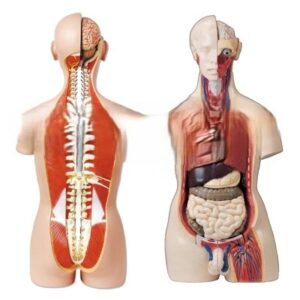

Related Products

Related products